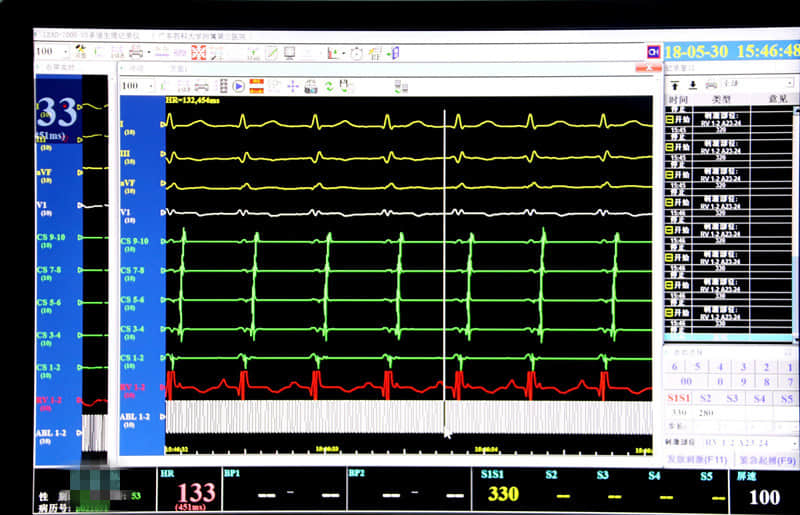

医护人员在进行术前准备后,由内一科主任程家亮、院外支持专家携手立即对患者实施了心内电生理检查及射频消融术。术中,通过穿刺血管,沿动脉鞘将蓝靶消融导管至二尖瓣环心室侧精确标测至理想靶点,以30W,60度试行消融5S,行S1S1 350ms心室刺激可见VA分离,再行巩固消融90s,反复心室刺激均未诱发心动过速,消融成功。术后第二日患者下床活动,无穿刺处血肿及心律失常并发症。